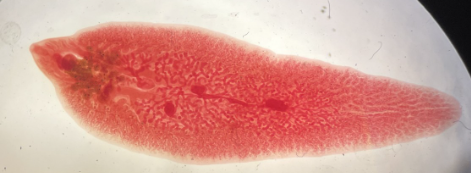

Fasciola hepatica

Fasciolopsis buski

Paragonimus westermani

Clonorchis sinensis